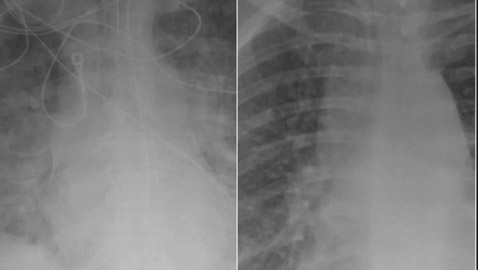

صور بالأشعة السينية تظهر الفرق بين الرئتين قبل وبعد ..